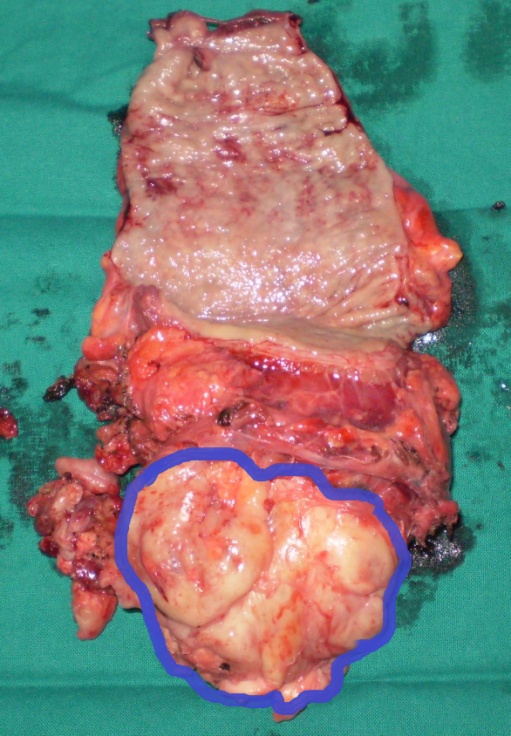

Surgical specimen. Complete resection of the tumor together with a segment of rectum (Courtesy Dr. V. Penopoulos)